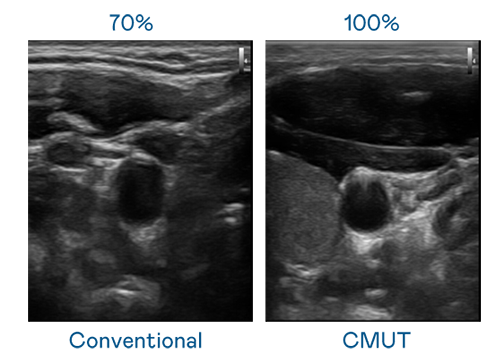

CMUT 技术是一种用电容式微机电元件来产生超音波讯号的技术。与传统 PZT 压电式技术相比,CMUT 频宽增加 30%,更宽频的超音波讯号让影像解析度大幅提升,是实现高影像品质医疗超音波扫描、促进精准医疗发展的关键技术。

大频宽带来超清晰影像

超音波影像的解析度高低,首先取决于探头能发出的讯号频宽。bevictor伟德 CMUT 可提供高清晰的超音波讯号,提供高频宽、高灵敏度、影像纹理细节更高的超音波影像,协助医护人员缩短影像判读时间及利用精准的医疗影像进行诊断。